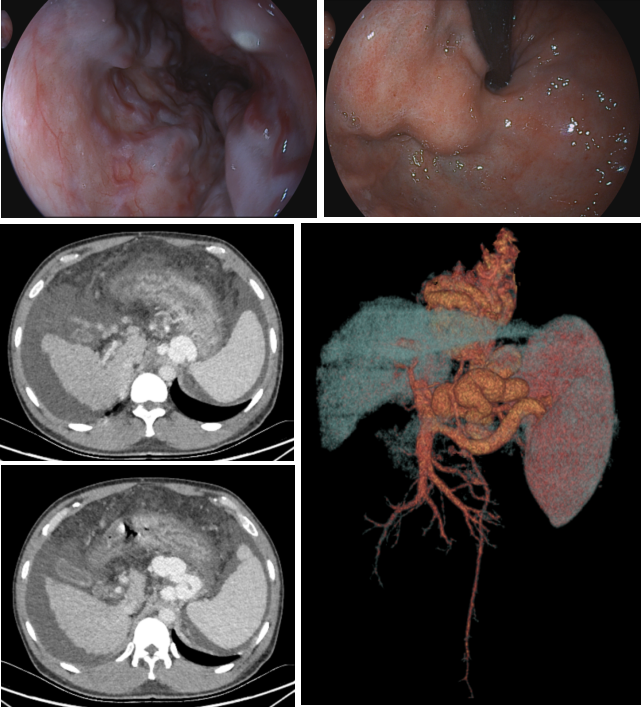

患者,男,43岁,乙型肝炎后肝硬化失代偿期、门脉高压,既往多次上消化道出血,本次因再次急性上消化道出血就诊兰大二院。接诊后,消化内科进一步完善相关检查,行胃镜显示:食管静脉重度曲张并白色血栓头形成、胃底静脉重度曲张。行门静脉CT显示:门脉主干及右支大量血栓形成、食管胃底静脉严重迂曲扩张、脾大、腹水。针对该患者,传统的内科保守治疗和内镜下治疗难以达到预期疗效,TIPS手术是针对此类门脉高压多并发症及门脉血栓的有效微创治疗方案。结合患者既往病史及检查检验结果及多学科讨论后,11月17日,消化内科血管介入团队为该患者实施了TIPS、食管——胃底曲张静脉栓塞手术。术中,测得该患者肝静脉压力梯度(HVPG)及门静脉压力梯度(PPG)均为20mmHg。术后,门脉造影见门脉血流经支架进入下腔静脉,异常食管胃底曲张静脉基本无显影,且门静脉压力梯度(PPG)降至13mmHg。术后复查患者各项临床指标达到正常满意度,TIPS支架血流正常,于11月21日康复出院。